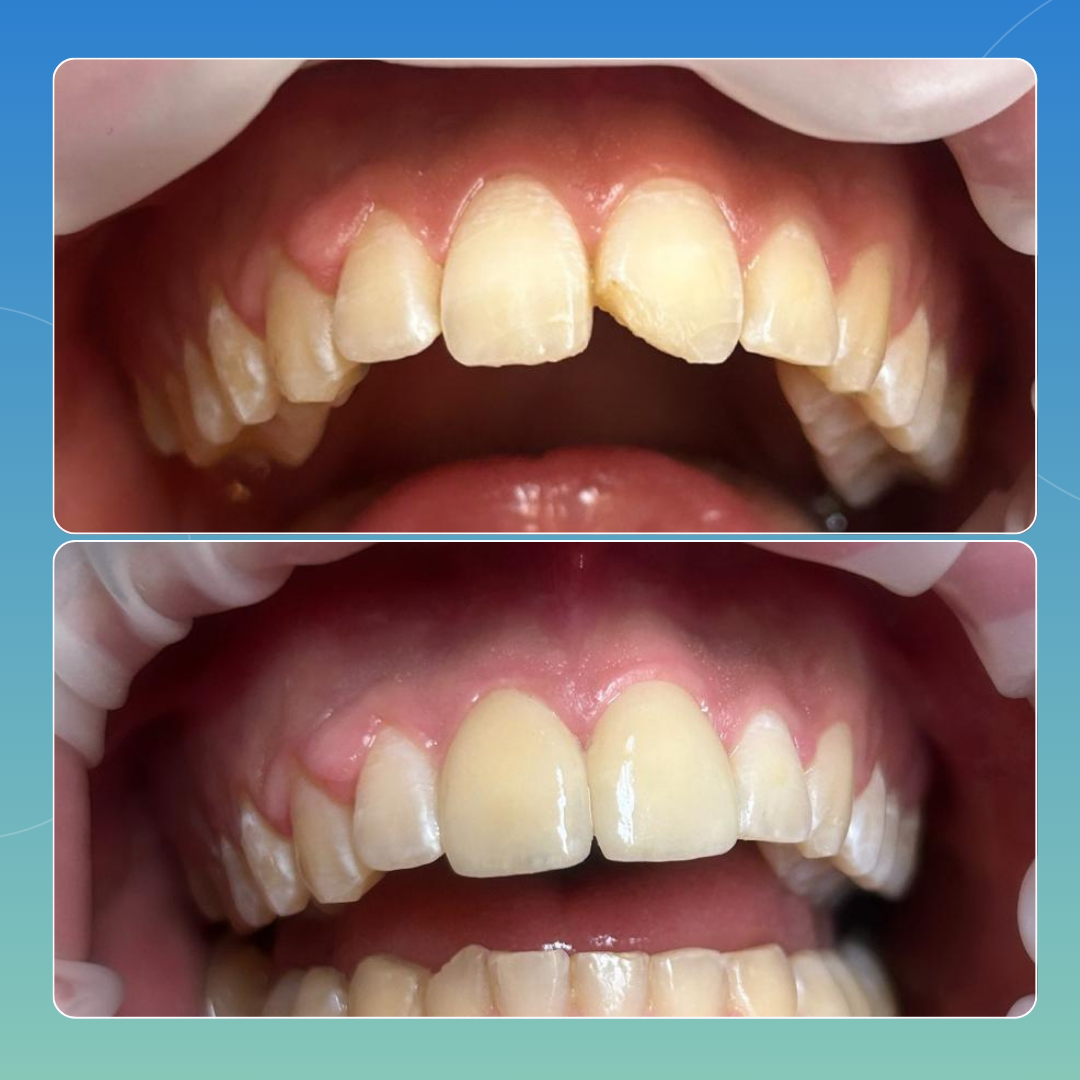

CASI CLINICI

Approccio personalizzato, esiti documentati

Di seguito riportiamo casi analizzati e svolti all’interno del nostro poliambulatorio che pensiamo possano rendere a pieno ciò che è per noi il nostro lavoro: passione e attenzione ai dettagli, volendo sempre il risultato migliore possibile che possa dar contentezza al paziente e a noi stessi